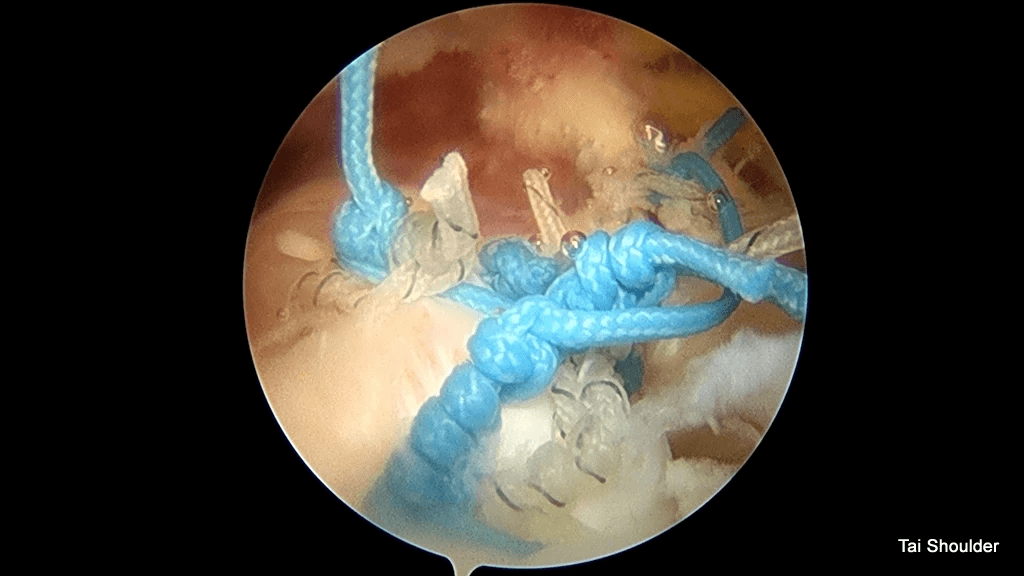

Knotless SwiveLock® Suture Anchor

分別有2條線

1.Mean load to failure was 231 N( 29 N to 360 N)

2.Load to failure was the highest with the knotless FiberTape 276 N